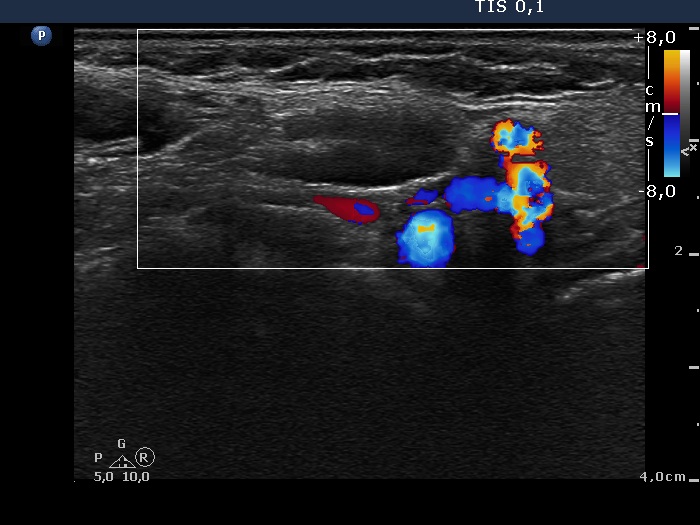

Ultrasonography: The thyroid was intact. There was a reactive-type lymph node in the right submandibular area.